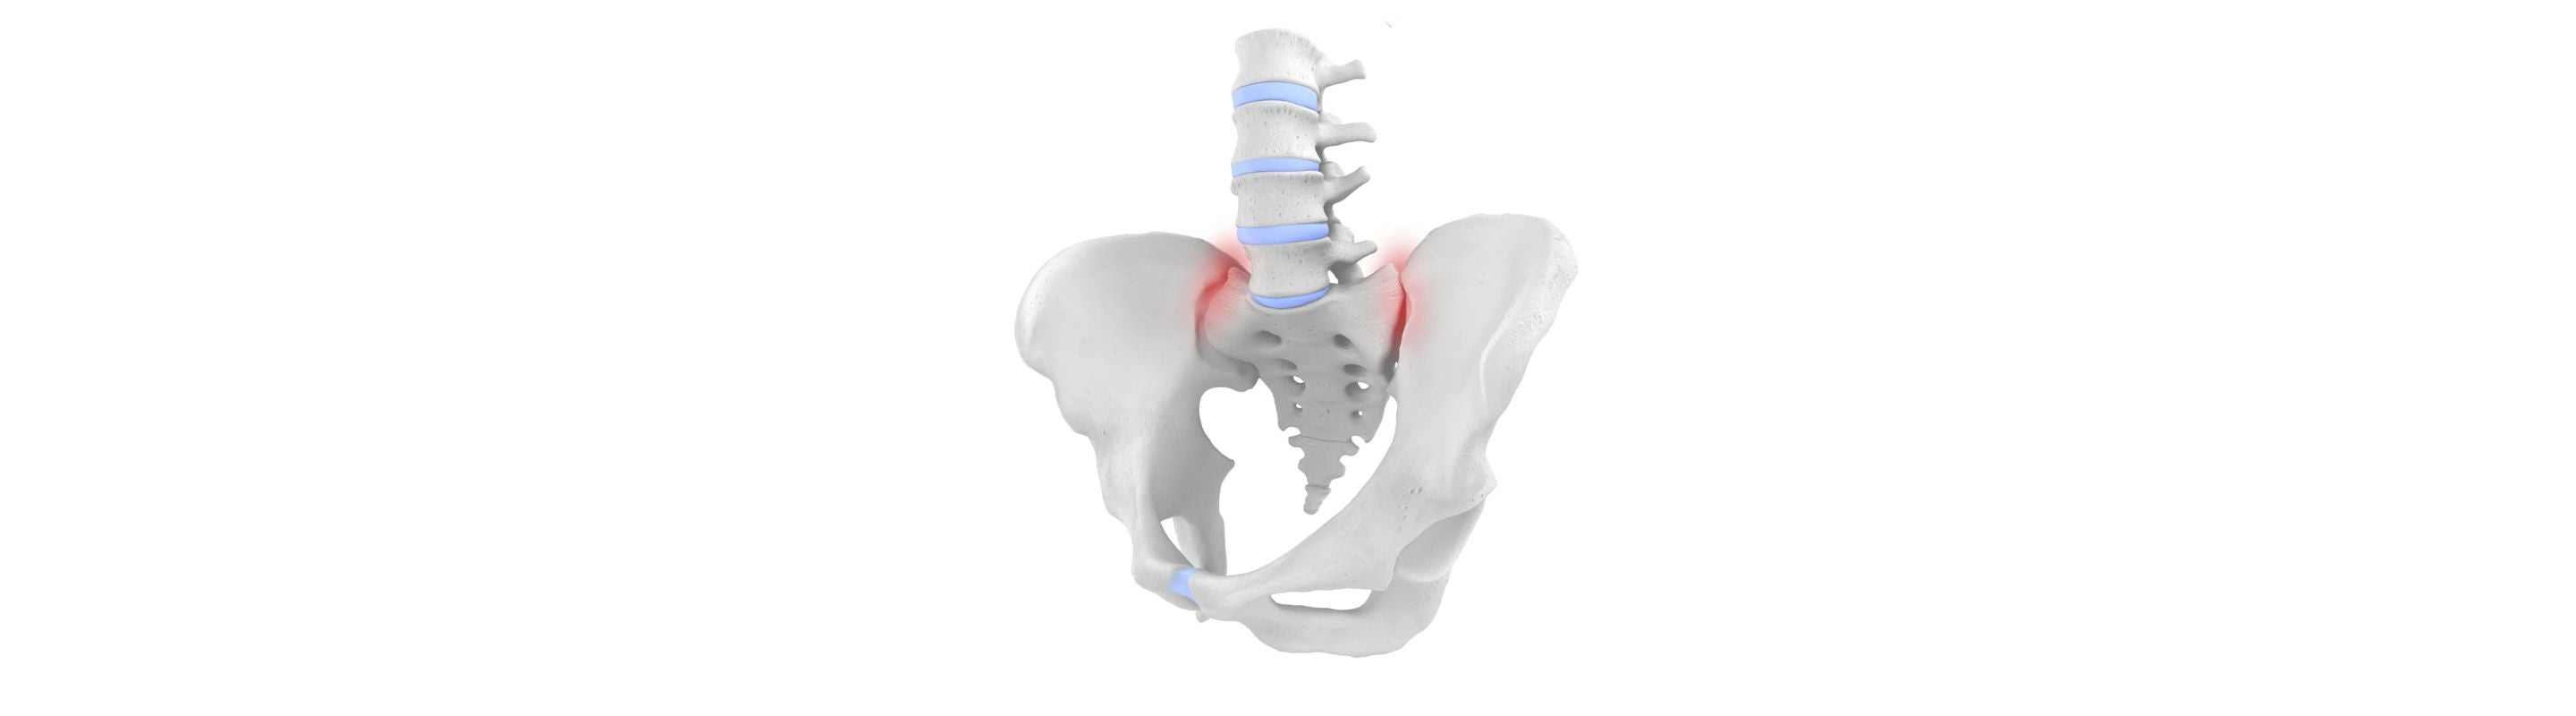

The SI joint is not very flexible by nature. Damage or degeneration of the SI joint can be significantly detrimental to a patient’s quality of life.

Mild cases can be resolved with conservative treatment. However, in cases of long-term wear and tear, severe degeneration of the joint can lead to a serious loss of lower back stability and mobility.

There are a few known factors that can lead to pain in the back, specifically in the sacroiliac joint. Some of them include:

- Injury in an accident or trauma can displace the SI joint and lead to immense pain.

- Poor proprioception adds excess pressure onto the SI joint and ligaments, which can lead to overloading of the joint.

- Sudden forceful exertion on the SI joint, typical of high-intensity contact sports like football and rugby, increases the risk of SI blockage.

Chronic pain in the sacroiliac joint is more commonly associated with:

- Long-term wear and tear of the SI joint, also called arthrosis, leads to weakening of the joint and surrounding ligaments.

- Loosening of the symphysis during pregnancy, leading to instability of the pelvic girdle and increased risk of developing pain in the SI joint.

- Infections and associated inherent pre-existing conditions, like rheumatic diseases, can make patients more susceptible to symptoms.

- Broken bones or herniated discs can result in weakening of the muscles, which increases the chances of degeneration of the SI joint.